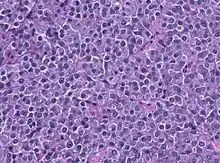

A prolactinoma is a tumor (adenoma) of the pituitary gland that produces the hormone prolactin. It is the most common type of functioning pituitary tumor.[1] Symptoms of prolactinoma are due to abnormally high levels of prolactin in the blood (hyperprolactinemia), or due to pressure of the tumor on surrounding tissues. Based on size, a prolactinoma can be classified as a microprolactinoma (<10 mm diameter) or a macroprolactinoma (>10 mm diameter).